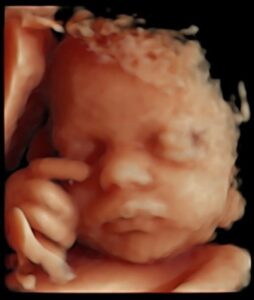

C’est la meilleure période pour réaliser une échographie plaisir en 4D ! Vous allez pouvoir observer les traits et les premiers mouvements de votre bébé. Durant ces semaines, il est même possible de l’observer cligner des yeux. Pendant cette période de développement très rapide, de nombreux parents réalisent plusieurs séances afin de suivre cette évolution.

La meilleure période pour venir faire une échographie 4D est à partir de la 22ème semaine de grossesse. C’est à ce moment-là que l’on distingue une vue d'ensemble du bébé, ses gestes... En se rapprochant de la 32ème semaine de grossesse, les traits et le visage de votre bébé se dévoilent plus précisément !

Notre Galerie.

Découvrez notre galerie vous présentant quelques photos inoubliables issus de nos dernières échographies 3D et 4D réalisées au sein de notre centre MonBébéEn4D !